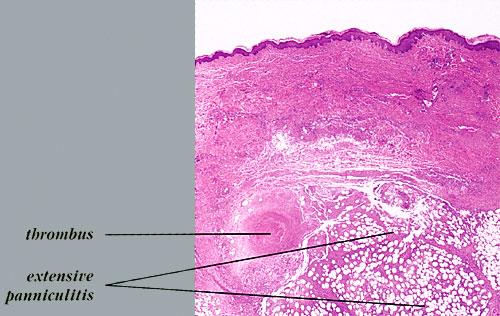

Nodular vasculitis = التهاب الاوعية العقيدي